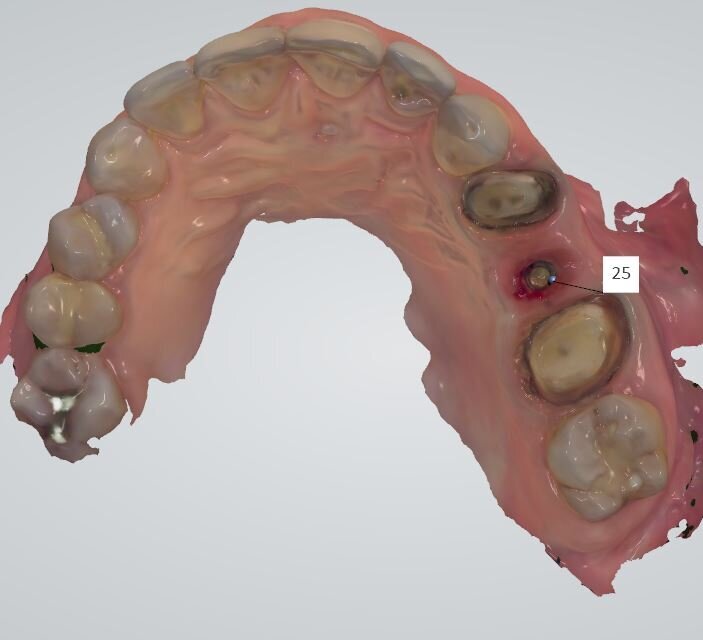

La paziente di 55 anni, non fumatrice, non affetta da alcuna patologia sistemica, da noi trattata con una procedura implantare sostitutiva dell’elemento naturale si era presentata alla nostra osservazione al fine di poter valutare un dolore riferito in sede 2.5 di tipo continuativo tollerabile ma con scarse variazioni di picco algico. L’elemento era stato curato endodonticamente e protesicamente da meno di 1 anno. All’esame obiettivo si presentava una neo protesizzazione individuale su 2.4 e 2.5, mentre su 2.6 si presentava una pregressa protesizzazione in oro-resina con vistosa retrazione gengivale che scopriva un margine corono-protesico impreciso. Il dolore riferito si estendeva tra i 2 premolari in oggetto. Al sondaggio si evidenziava un tragitto patologico di 9 mm in sede mesio-vestibolare della corona in 2.5 (Fig. 1) mentre il sondaggio degli altri elementi si configurava come fisiologico, privo di sanguinamento. L’esame radiografico endorale, mirato al sito ed eseguito con un centratore evidenziava un baffo medicamentale posto mesialmente e associato ad una lacuna ossea adiacente (Fig. 2). La diagnosi di frattura verticale non consentiva alcun recupero radicolare, mentre le radici adiacenti pur avendo delle diafanie periapicali non presentavano sintomi, al fine di un recupero protesico dell’emiarcata si è preferito eseguire una nuova terapia radicolare endodontica (Fig. 3). Fatta la diagnosi si apre un’attenta valutazione sulla tecnica chirurgica, alcune considerazioni vanno fatte sul tipo di estrazione per riuscire ad essere quanto più conservativi, per il mantenimento della cresta ossea vestibolare e per l’architettura gengivale. In tal caso le tecniche atraumatiche prevedono l’utilizzo di strumenti volti alla percussione estrattiva della radice, o al sezionamento obliquo o all’uso di strumenti ultrasonici che lesionano l’attacco dei legamenti parodontali senza intaccare la struttura ossea. Su quest’ultima è ricaduta la nostra tecnica consentendoci di ottenere un sito pulito da frammenti sia ossei che radicolari e riducendo al minimo le lesioni vascolari, senza lembi d’accesso e con un alveolo esangue.

Fig. 1 - Sondaggio parodontale della lesione mesio-vestibolare del dente 2.5.

Fig. 3 - Visione occlusale del sito estrattivo nella fase immediatamente successiva la rimozione radicolare.